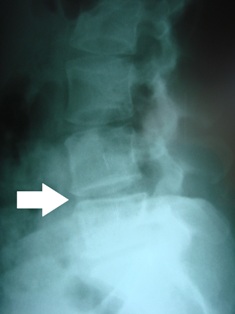

the misalignment of one vertebra upon the other